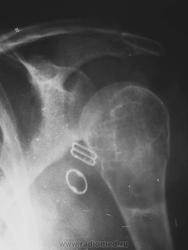

или гигантоклеточная опухоль. Требуется морфологическая верификация

Интересно, что структура разная, кость не вздута, кортикал истончен, но сохранен. Болей до травмы совершенно не было. Думаю, травматологи прооперируют, надеюсь узнать результаты гистологии - сообщу. Спасибо. Татьяна Валентиновна. Я сначала на аневризмальную кисту подумала, но не уверена была.

А, плечо "наголо" видели, какое оно?

Я не видела, в гипсе дама. И для КТ снять не разрешили(((

При ГКО бывает вторичная аневризмальная киста